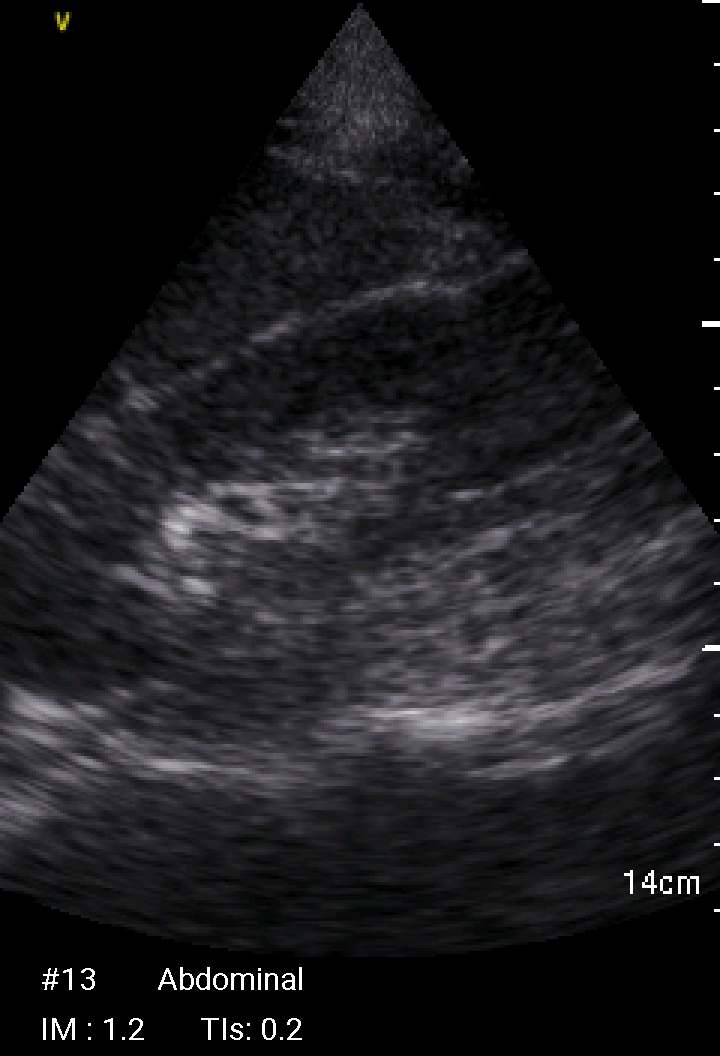

Echographie Sous-clavièreJugulaireFémorale JUGULAIRE G FEMORALE Dt MorissonKohlerDouglas Sous-clavièrePleural J’aime chargement…